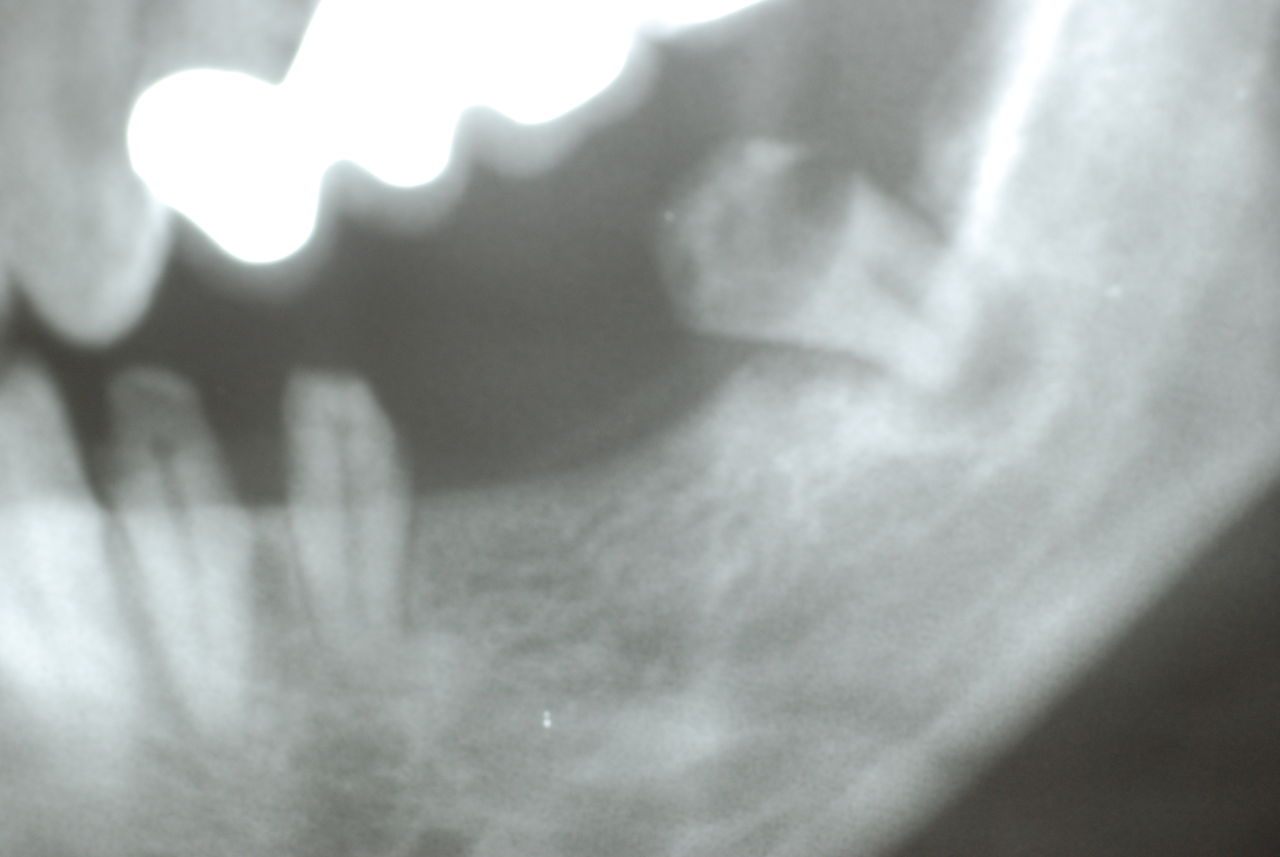

隣の14歳大臼歯がひどい虫歯になり治療不可能になりつつある状態のレントゲン